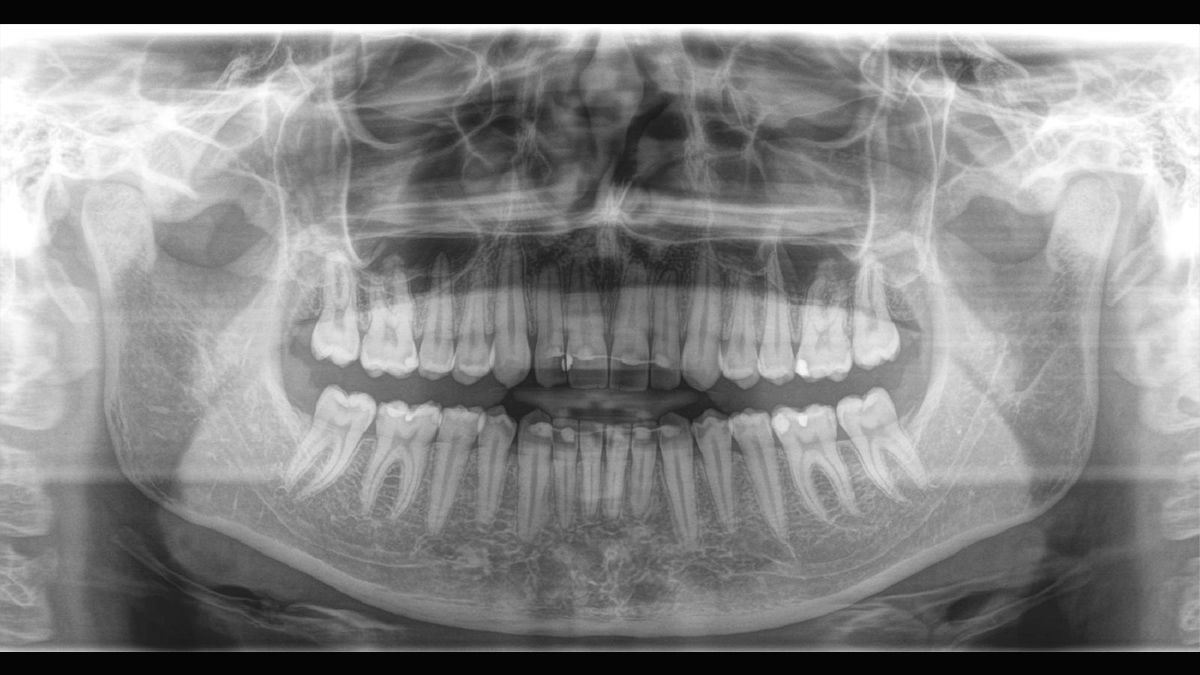

Tecnología Sharp Layer (SL)

La tecnología SL le permite generar multiples imágenes durante una única rotación. Los fragmentos con mejor enfoque se combinan automáticamente para formar una imagen de rayos X con nitidez incomparable (ideal para observar piezas multiradiculares).

Direct Conversion Sensor

La tecnología DCS convierte los rayos X directamente en señales eléctricas sin pérdida de información debida a la conversión de la luz. Permite obtener imágenes de radiografía panorámicas de elevado contraste con una calidad excepcional.

Algoritmo de software ASTRA

ASTRA mejora considerablemente la calidad de las imágenes panorámicas 2D y cefalométricas. Este algoritmo de reconstrucción estructurado anatómicamente genera una imagen con mayores contrastes sin la aparición de bordes indefinidos.